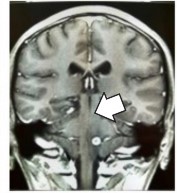

Se trata de un varón de 28 años, a quien recientemente se le diagnosticó VIH, sin tratamiento antirretroviral. Llega al hospital con la siguiente sintomatología: ptosis palpebral derecha, visión doble vertical, arrastre de pie izquierdo, incapacidad para mantener la bipedestación, hemiparesia izquierda (fuerza muscular MS 2/5 MI 2/5), hipotonía izquierda, reflejos osteotendinosos (ROT): hiporreflexia izquierda (+/++), sensibilidad izquierda superficial y profunda disminuida, equilibrio y coordinación alterados, III par derecho parético al 75 %, pupila derecha arreactiva a la luz de 5 mm y reflejo consensual ausente. Una resonancia magnética con contraste detecta una imagen compatible con toxoplasmosis cerebral (Figura 1). Por otro lado, la prueba serológica de líquido cefalorraquídeo (LCR) para toxoplasmosis cerebral mediante inmunoquimioluminiscencia (IMMULITE 2000) detecta los anticuerpos Ig M >1,1, con resultado “reactivo”, lo que indica una infección activa. Por tanto, se indica un tratamiento protocolizado en la institución y se evidencia restablecimiento; la evolución es favorable con mejoría de la sintomatología.

Figura 1 Resonancia magnética nuclear (RMN) de encéfalo contrastada. Se observan imágenes captadoras de contraste de 3-5 mm a nivel de mesencéfalo (flecha blanca).